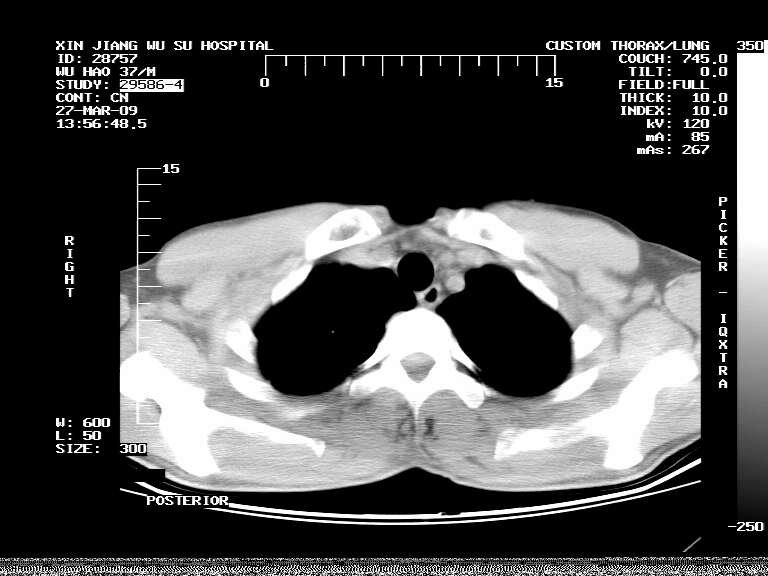

男,37岁,体检胸透发现阴影。

患者体检发现 无症状 左肺下叶占位,边缘模糊,可见血管聚束、分叶、胸膜牵拉,增强呈不均匀性强化。 首先考虑左肺下叶周围型肺癌,建议穿刺活检。

患者体检发现 无症状 左肺下叶占位,边缘模糊,可见血管聚束、分叶、胸膜牵拉,增强呈不均匀性强化。 首先考虑左肺下叶周围型肺癌,建议穿刺活检。支持!

左肺下叶见一结节病变,边缘欠清不光滑,与胸膜粘连且胸膜局限性增厚,注药后呈环形强化,动脉期壁呈明显点环状强化,静脉期壁强化减低,中心密度低无强化,灶周无明显的卫星灶和水肿区(晕征)---考虑周围性肺癌,不除外感染性病变,建议穿刺活检。

病灶强化太明显,病人较年轻。考虑炎性假瘤与周围型肺癌鉴别,以前者可能性,建议抗炎治疗后复查。

左肺下叶软组织病灶,密度较高,内见点状钙化,其周围见子灶,邻近胸膜扁平样增厚.c+病灶强化明显,中心强化弱.诊断:左肺下叶结核瘤.

左肺下叶大片实变影,内靠胸膜见不规则更高密度结节灶,边缘强化,相邻胸膜增厚,胸膜下脂肪线存在。考虑炎症,结核可能。